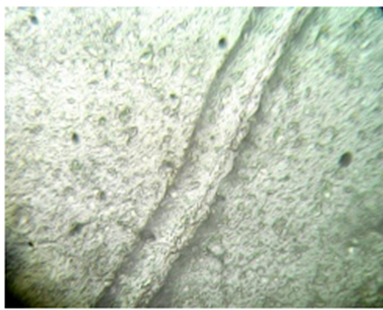

In-vitro scratch assay

Percentage (%) of cells that moved in the direction of the wound and helped it close microscopically images representing the In vitro wound healing nature of Sample: L929 cells were incubated in presence or absence of Samples and standard drug Cipladine and images were captured at 48 hours. According to images and results Sample showed Moderate activity Percentage (%) of cells that moved in the direction of the wound and helped it close.

Figure 2: Normal Morphology of L929

Control - Wound Scratch                                       After 48 hours - Control

Standard - Wound Scratch (Cipladine)                 After 48 hours - Standard (Cipladine)

Sample - Wound Scratch                                 After 48 hours - Sample

Table 2 Percentage (%) of Cells Reduction in Wound Closure.